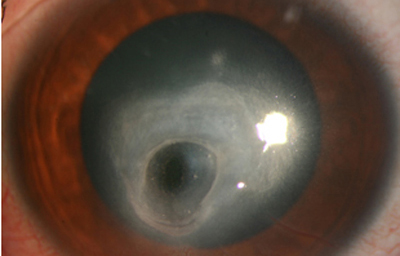

En su evolución se observará aumento del edema, agrandamiento y coalescencia de los infiltrados formando un anillo, (Figura 9, 10 y 11) que progresa hacia la formación de un absceso (Figura 12, 13 y 14), queratolisis superficial, adelgazamiento y perforación corneal (Figura 15 y 16).

Limbitis y escleritis anterior difusas.

La vascularización y el hipopion son poco frecuentes en los estadios tempranos de la queratitis. Con el tiempo, en los estados avanzados de invasión estromal, aparecen vasos estromales (Figura 17)

En los estados avanzados con abscesificación y queratolisis, se enmascara el cuadro corneal, ocultando las características clínicas típicas de la queratitis por Acanthamoeba. (Fig 18)